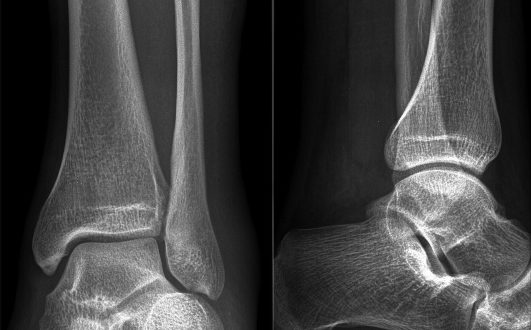

Основные рентген-симптомы патологии костей и суставов Диагностику патологии облегчает тот факт, что больной может точно указать врачу время получения травмы, поскольку она не пройдет незамеченной. Вывих или подвывих…

Что такое вывих голеностопа и его степени с фото Выполняя основную функцию опоры всего тела при ходьбе, голеностопный сустав – сложный механизм, соединяющий стопу и кости голени. Берцовые…

Основные признаки и классификация У каждого вида повреждения существуют свои симптомы: Вывих голеностопа характеризуется сильной болью, видимой деформацией стопы и нарушением функций (невозможно встать на ногу и ходить);…

Причины перелома с подвывихом Отдельно стоит выделить спортивные травмы с приложением добавочного внешнего усилия, придающего определенное положение стопе в момент травмы: например, стопа может находиться в положении отведения/приведения, супинации/пронации. Переломы голеностопа…